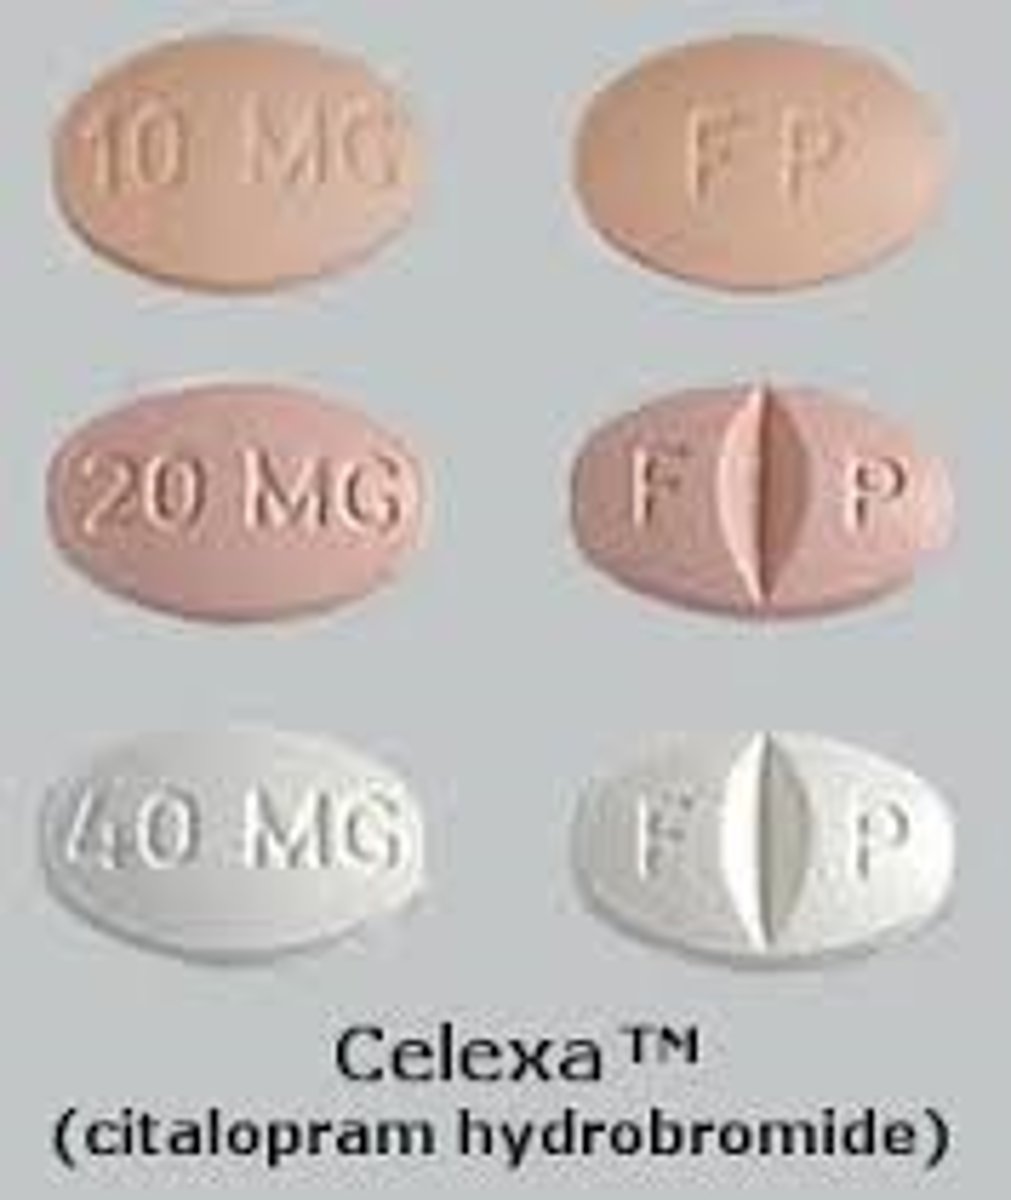

Citalopram

Brand: Celexa

Class: SSRI

Interaction: Serotonin Syndrome with MAOIs

Indication: Antidepressant

Schedule: NCLM